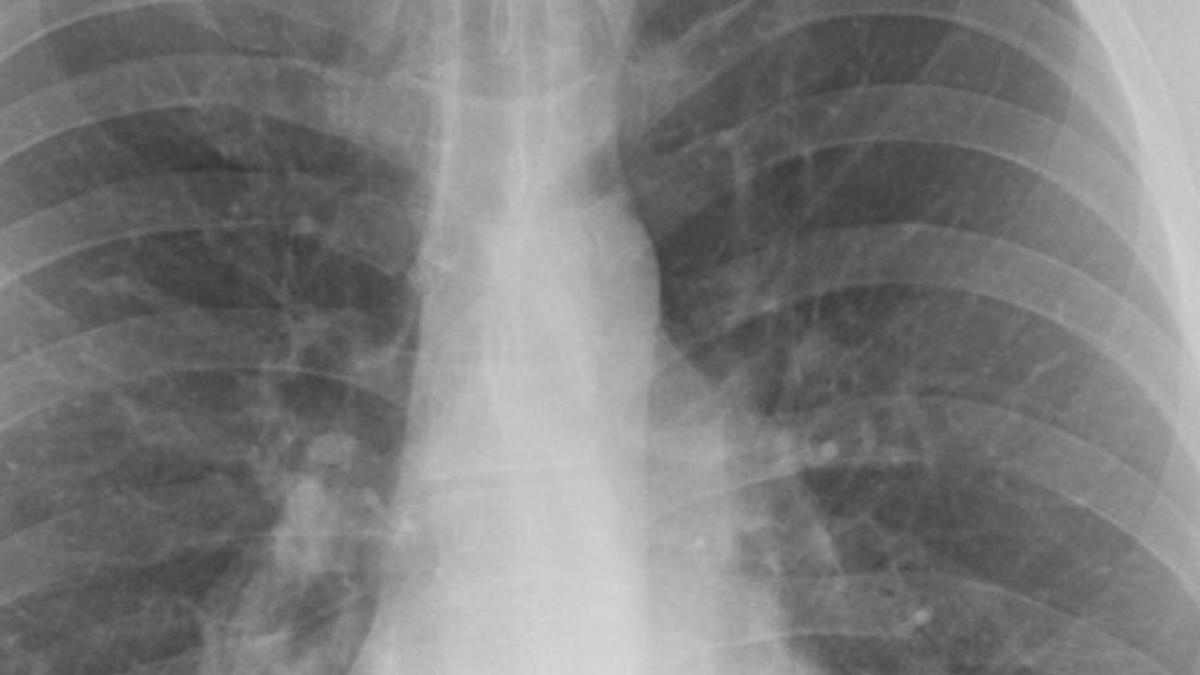

Bacteria de la Institutul ”Marius Nasta” a făcut prăpăd: 13 pacienți au murit de la începutul anului din această cauză06 Mar

Încă o persoană infectată cu acinetobacter a murit la Institutul Marius Nasta. Bilanțul deceselor a ajuns la 4 25 Feb

Ce este Acinetobacter, bacteria care a ucis mai mulți pacienți la Institutul „Marius Nasta” din București21 Feb

A murit și al doilea pacient de la Institutul Marius Nasta, care a fost infectat cu o bacterie periculoasă15 Feb